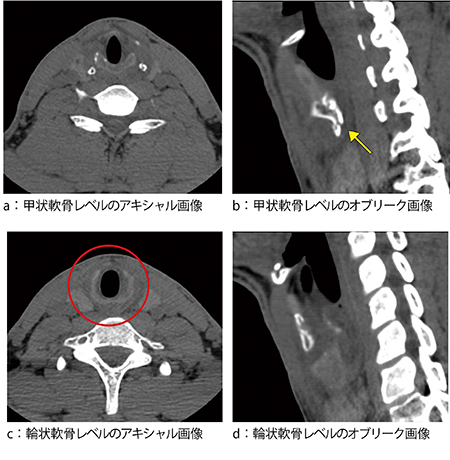

症例は,28歳,男性。サーフィン中にサーフボードが喉に当たり,直後より嗄声を自覚したため,当院耳鼻咽喉科を受診した。甲状軟骨,輪状軟骨の骨折を疑い,喉頭部CT検査を施行し,アキシャル画像,オブリーク画像を作成した。甲状軟骨レベルのオブリーフ画像では骨折があることが認められるものの,骨折部の同定,また骨折部の形態的な評価は困難であった(図1)。

図1 喉頭部CT画像

甲状軟骨レベルのオブリーク画像(b)で甲状軟骨左下角に骨折があるのが確認できる(←)。輪状軟骨レベルのアキシャル画像(c)では,明らかな骨折線は認められないが,気管壁に左右差が認められる(○)。また,左側壁はやや腫脹しており線状影があるように見える。